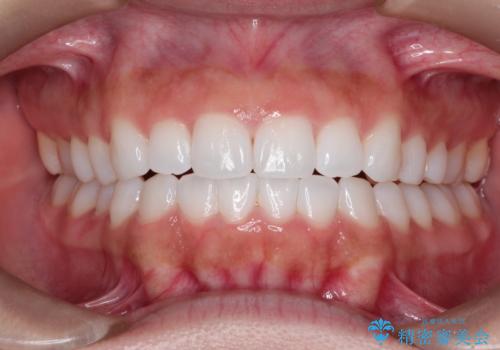

ワイヤーによる抜歯矯正でガタガタと深いかみ合わせの改善